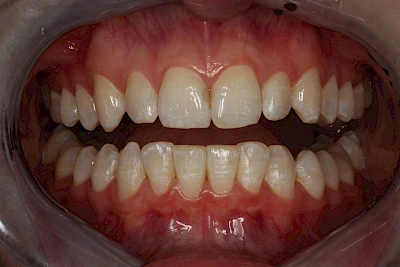

Verfärbungen an Zähnen können außen aufgelagert oder im Zahn eingelagert sein.

Gerade bei Kindern und Jugendlichen werden zunehmend häufiger bräunliche Verfärbungen mitunter auch mit Formveränderungen (die Oberfläche ist rauh oder zerklüftet) der Zähne beobachtet. Meist sind Schneidezähne oder Backenzähne betroffen. Dies könnte ein Hinweis auf sogenannte Kreidezähne (MIH: Molaren-Inzisiven-Hypomineralisation) sein.

Daneben gibt es noch seltene genetisch bedingte Schmelz- bzw. Dentinbildungsstörungen (Amelogenesis imperfecta, Dentinogenesis imperfecta), die neben Verfärbungen vor allem auch durch Veränderungen der Oberflächenstrukturen auffallen. In diesen Fällen ist eine engmaschige Betreuung durch den Zahnarzt wichtig.